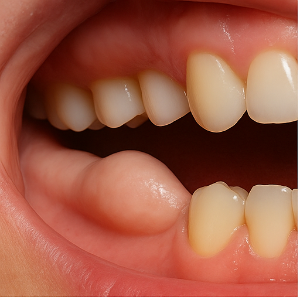

입 안쪽 잇몸에 단단한 혹처럼 느껴지는 돌출이 나타날 때, 이를 흔히 골융기(骨隆起)라고 합니다. 실제로는 혹이 아니라, 잇몸 아래 뼈가 과하게 자라서 돌출된 구조예요. 단단하고 움직이지 않으며, 보통 통증은 없답니다. 원인은 뚜렷하지 않지만, 선천적으로 갖고 태어나는 경우도 있고, 나이가 들며 조금씩 자라기도 해요.

골융기는 다음과 같은 위치에서 주로 발견돼요:

- 아랫니 안쪽, 흔히 혀 쪽 방향인 아래턱 뼈 부분

- 위턱 안쪽, 입천장 쪽 몇몇 부위에도 나타날 수 있어요

특징은 다음과 같아요:

- 딱딱하고 단단한 혹처럼 올라와요.

- 표면이 매끈하거나 둥글게 보이기도 하고, 울퉁불퉁하거나 튀어나온 형태인 경우도 있어요.

- 대부분 통증은 없지만, 아주 단단한 음식이나 자극이 있을 경우 불편함이 있을 수 있어요.